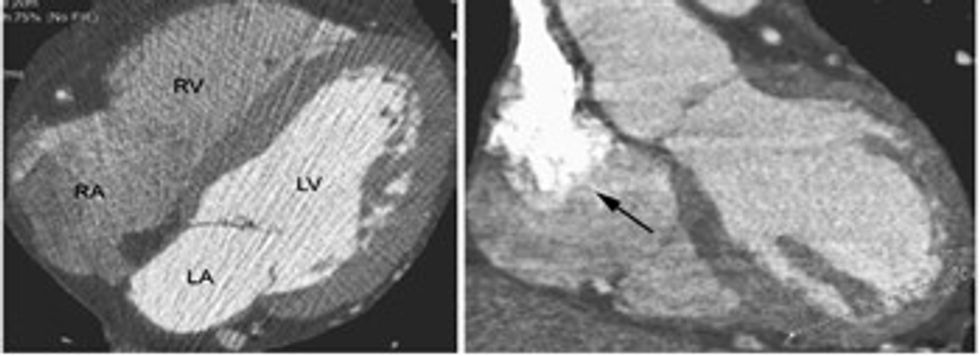

Mundëson vizualizimin e hapësirave të zemrës (barkusheve dhe veshëzave) si dhe e arterieve koronare që e furnizojnë atë me gjak.

Me koronarografi me tomografi të kompjuterizuar mund ta shohim zemrën në tërësi nga të gjitha anët, ku shohim muret e saj të formuara nga muskuli i zemrës dhe arteriet koronare në sipërfaqe.

Mund t’i analizojmë ndaras arteriet koronare dhe ta vlerësojmë patologjinë e tyre të mundshme.